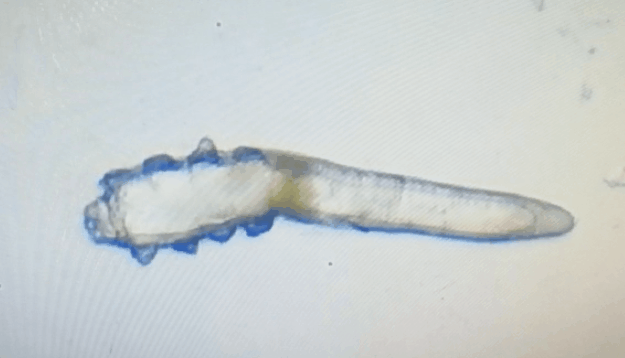

這就不得不提到眼科醫(yī)生經(jīng)常使用的螨蟲檢測(cè)工具——螨蟲鏡檢。它通過顯微利器,無死角全方位掃描你的睫毛,讓螨蟲無處遁形。

林女士是一家公司的白領(lǐng),常常需要濃妝出席各種會(huì)議,然而光鮮亮麗的背后,林女士的眼睛正遭受著和陳先生同樣的癥狀。在螨蟲鏡檢中,當(dāng)看到自己的睫毛上爬滿了十幾只透明的生物-螨蟲,林女士嚇了一跳。幸而,經(jīng)過廈門眼科中心干眼中心的治療,林女士解決了多年的眼睛干癢問題。